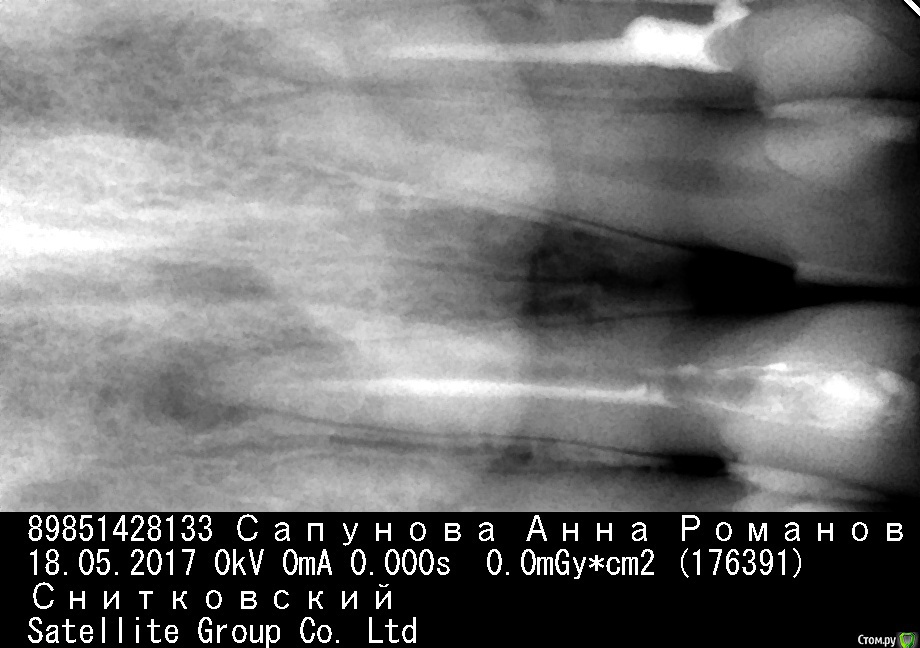

St. Опубликовано 24 мая, 2017 Поделиться Опубликовано 24 мая, 2017 Это снимки до лечения или на данный момент? В этих зубах в подавляющем большинстве случаев 1 канал, в вашем я тоже второго не вижу. Если есть сомнения можно сделать КТ ( компьютерную томографию). Там точно будет видно, в том числе и количество каналов.Мрт не нужно, нужно КТ. Это разные исследования. В стоматологии первое практически не используется. Штифты действительно проходят тонким бором или сверлом. Это достаточно кропотливая процедура, лучше если доктор это делает в оптике. Ссылка на комментарий

Anna84 Опубликовано 24 мая, 2017 Автор Поделиться Опубликовано 24 мая, 2017 Это снимки до лечения или на данный момент? В этих зубах в подавляющем большинстве случаев 1 канал, в вашем я тоже второго не вижу. Если есть сомнения можно сделать КТ ( компьютерную томографию). Там точно будет видно, в том числе и количество каналов.Мрт не нужно, нужно КТ. Это разные исследования. В стоматологии первое практически не используется. Штифты действительно проходят тонким бором или сверлом. Это достаточно кропотливая процедура, лучше если доктор это делает в оптике. это снимки на данный момент. Скажите , вы не видите признаков того, что в канале зуба присутствует пломбировочный материал, который недочистили ? мне так сказал врач к которому я ходила на консультацию. Ссылка на комментарий

St. Опубликовано 24 мая, 2017 Поделиться Опубликовано 24 мая, 2017 Если снимок на данный момент, то да, неубранный материал присутствует в большом количестве. И да, если запломбирвать так, то большой риск что там остались микробы и воспаление будет продолжаться.Естественно лечение с оптикой будет дороже, но и результат его более прогнозируемый. Убирая стекловолокно без увеличения есть риск истончить корень или того хуже сделать перфорацию( лишнее отверстие в стенке ). 1 Ссылка на комментарий